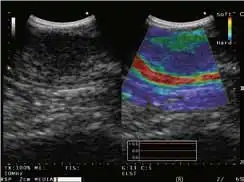

与凸阵扫描超声内镜配套使用

THE-P模式 POWER FLOW模式 COLOR FLOW模式

H-FLOW模式 ELST模式